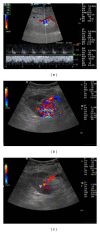

Renal transplantation is the treatment of choice for managing patients with end-stage kidney disease. Being submitted to a very serious surgical procedure, renal transplant recipients can only benefit from follow-up imaging and monitoring strategies. Ultrasound is considered as the principal imaging test in the evaluation of renal transplants. It is an easily applied bedside examination that can detect possible complications and guide further imaging or intervention. In this imaging review, we present essential information regarding the sonographic features of healthy renal transplants, detailing the surgical technique and how it affects the sonoanatomy. We focus on various complications that occur following renal transplantation and their sonographic features by reviewing pertinent literature sources and our own extensive imaging archives.